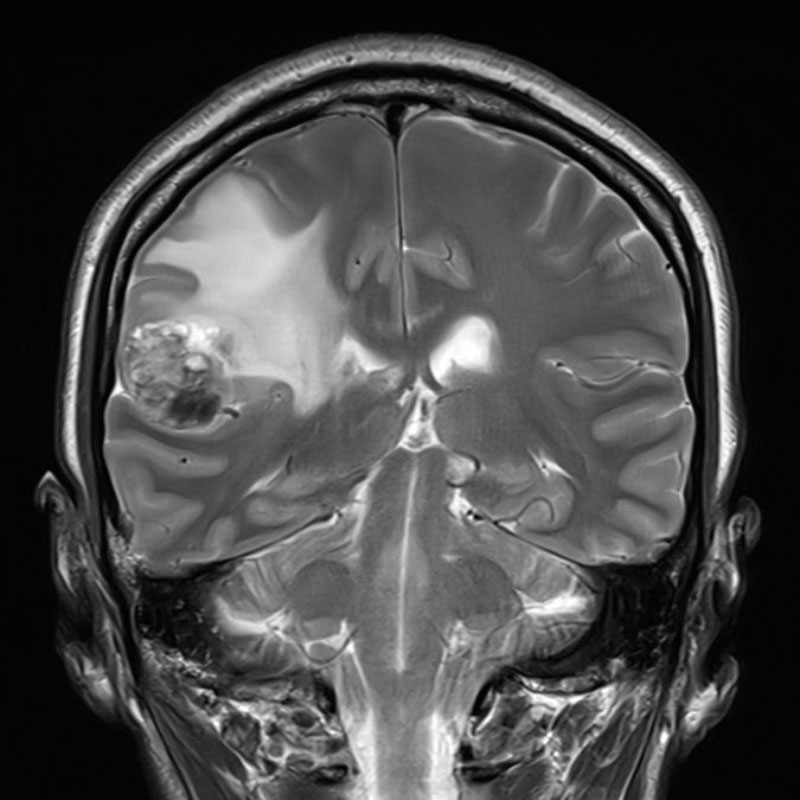

断層撮影

手術前1